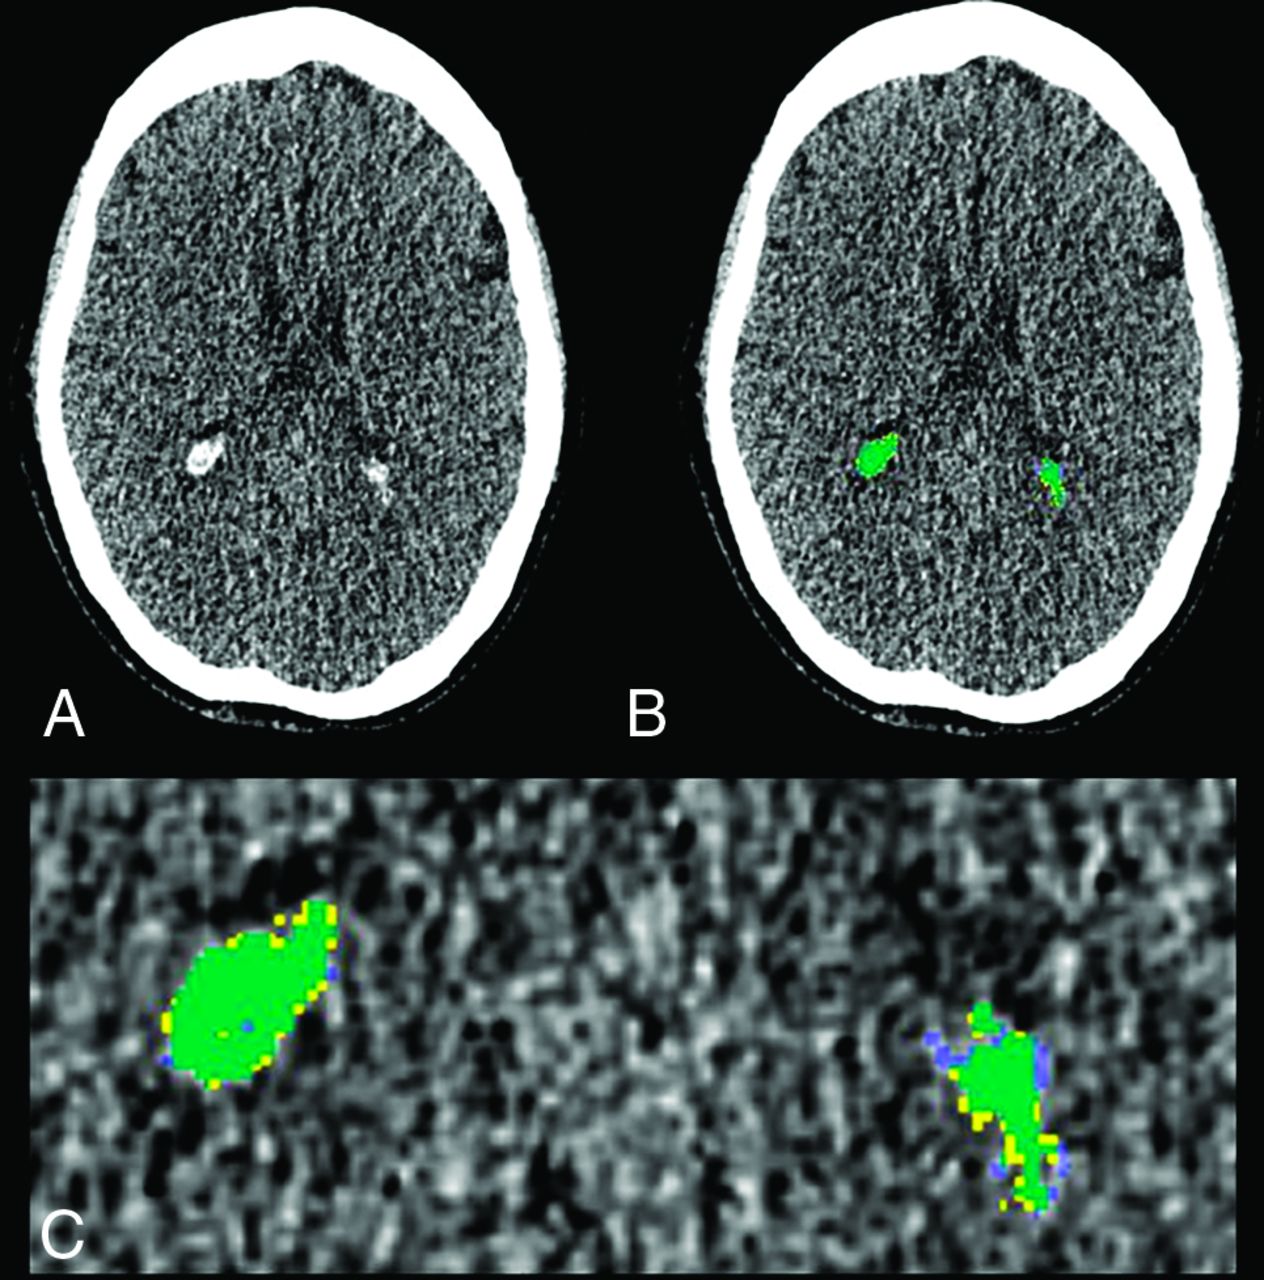

There was excellent absolute agreement between semimanual and automated calcium measurements (ICC = 0.982, F[43, 43] = 71.42, P < .001). On the basis of this agreement, for all subsequent analyses, CP calcium refers to the automated value. Figure 1 shows an example of CP semimanual and automated segmentation.

Example of CP calcification segmentation. A, Axial section from a low-dose CT acquired with PET/CT shows CP calcification in the occipital horn of the lateral ventricles bilaterally. B, Semimanually traced CP calcification is shown in yellow; fully-automated segmentation, in blue; and the overlap, in green. C, Magnified view of B shows close correspondence between semimanual and automated CP calcification segmentation.